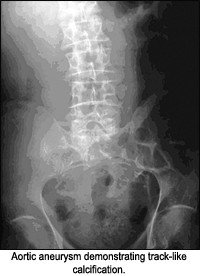

- linear or track-like;

Rim-like appearance can be described as a wall of calcification surrounding a hollow structure, as in a renal cyst. Track-like or linear calcification indicates a tubular structure, as in the walls of the ureters or arterial walls. Lamellar calcification is formed in the lumen of a hollow structure, as in renal stones or stones in the gallbladder. Cloud-like calcifications are formed in a solid organ or tumor, such as a leiomyomas of the uterus or calcifications in the pancreas. Once the appearance of the calcification is apparent, the next step is to consider what anatomical structure is in that location. I am assuming one has ruled out the possibility of an artifact before considering a calcification as such.

The following images are representative of the four classic appearances of calcifications (rim-like, linear, lamellar, and cloud-like):